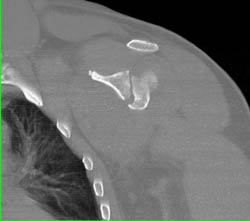

Diagnosis

Deep Vein Thrombosis (DVT)